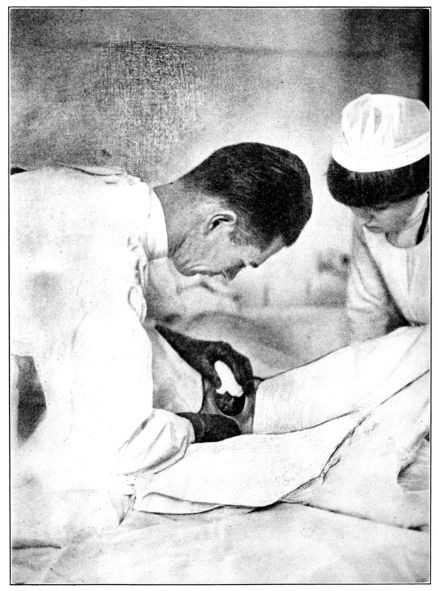

| 104, 105. | Giving ether for obstetrical anæsthesia | 289, 290 |

| 106. | Giving ether for complete anæsthesia | 293 |